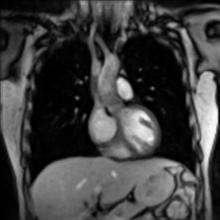

Cardiovascular

Cardiac MRI is complementary to other imaging techniques, such as echocardiography, cardiac CT and nuclear medicine. Its applications include assessment of myocardial ischemia and viability, cardiomyopathies, myocarditis, iron overload, vascular diseases and congenital heart disease.[23]